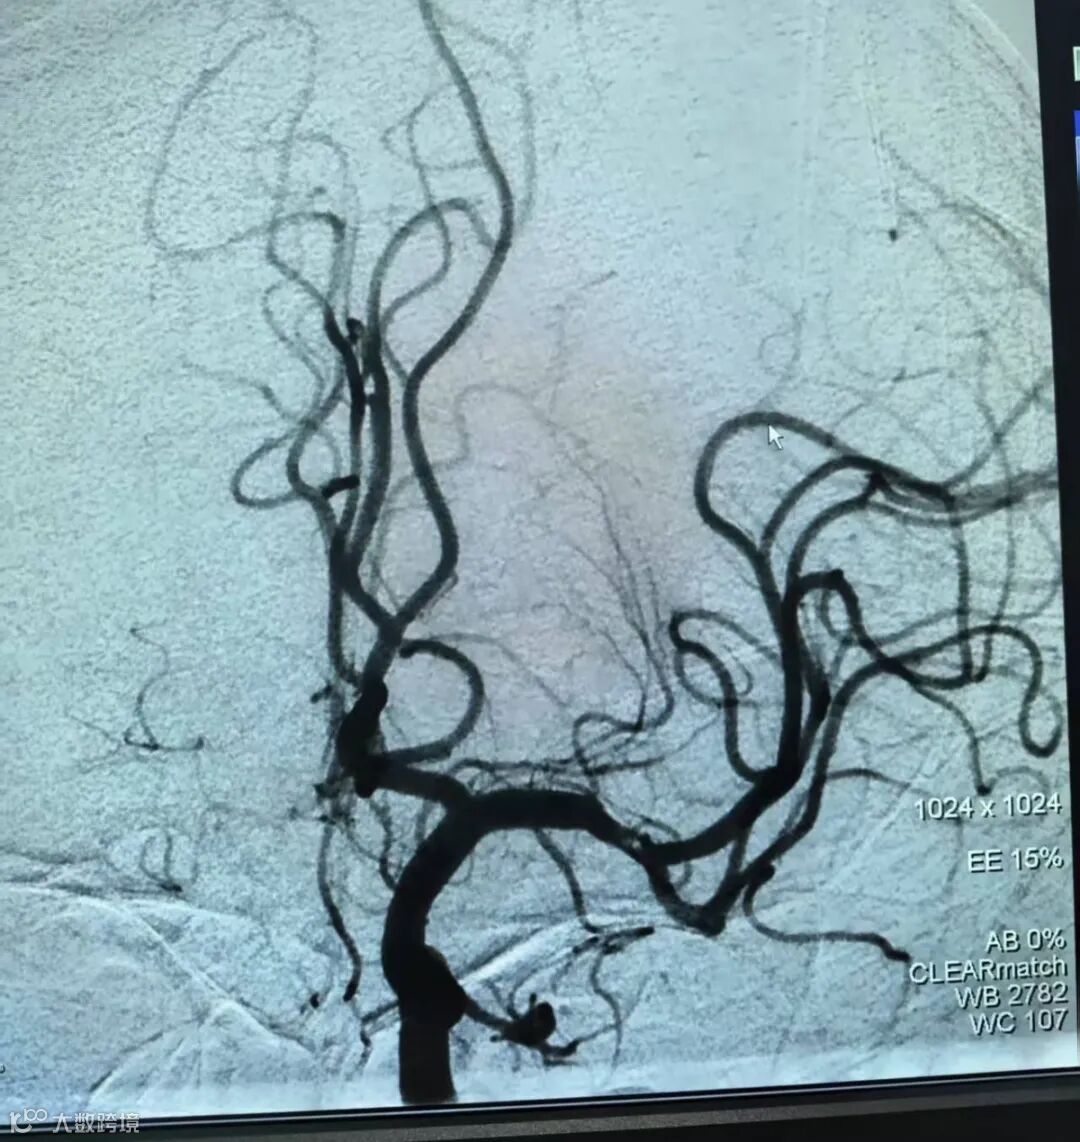

左侧大脑中动脉开通

取出0.5cm的血栓